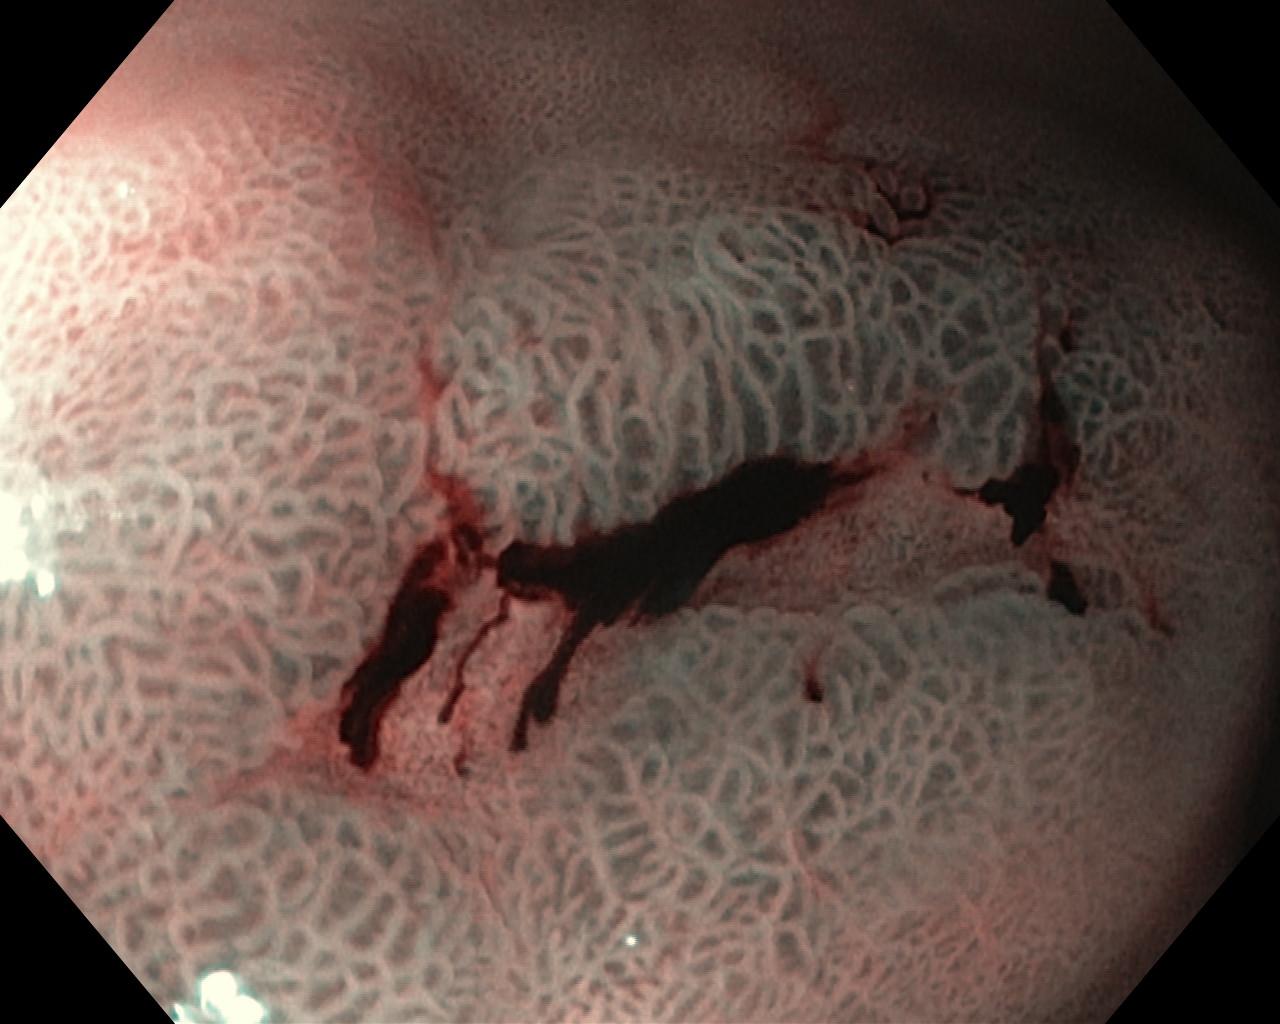

Wrzód trawienny